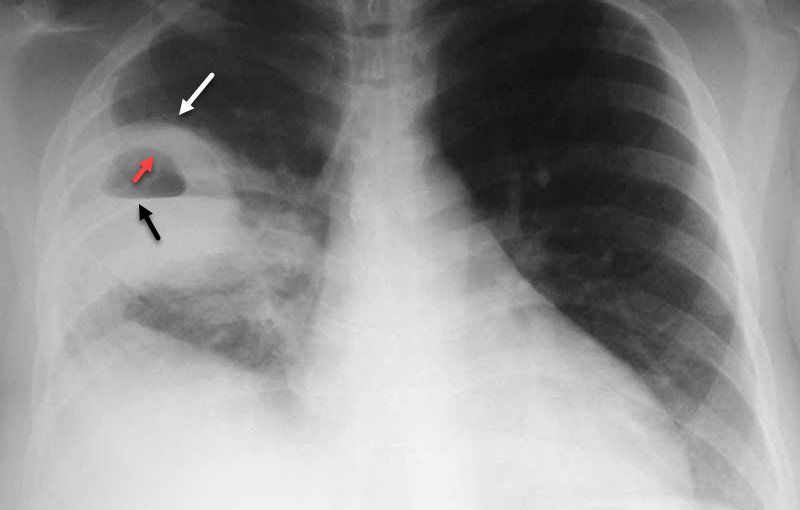

Chụp X quang phổi tư thế đỉnh phổi ưỡn giúp phát hiện tổn thương vùng đỉnh phổi

3. Chỉ định, chống chỉ định chụp X quang phổi tư thế đỉnh phổi ưỡn

Khảo sát tổn thương vùng thùy giữa và đỉnh phổi

- Bước 2: Người bệnh đứng thẳng, lưng dựa vào cát-xét, ưỡn ngực. Tia X trung tâm chếch lên < 30 độ vào góc giữa cán - thân xương ức. Độ chếch tùy thuộc độ ưỡn của người bệnh. Người bệnh phải hít vào sâu (tăng thể tích phổi thăm khám), nín thở. Nếu chụp tư thế sau – trước, người bệnh áp ngực vào cát-xét, tia X trung tâm chếch từ sau ra trước, xuống dưới 30 độ vào mấu gai C7.